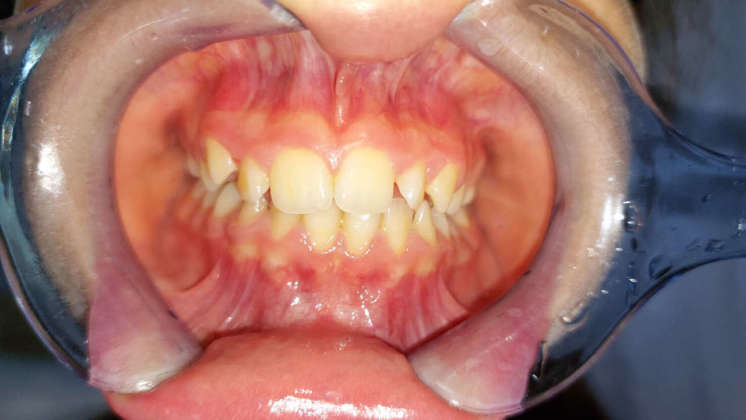

Tecniche di rilassamento psicologico e muscolare sono risultate efficaci nel ridurre i segni di bruxismo nei bambini di età inferiore ai sei anni (31), ma sfortunatamente l’educazione all’autoconsapevolezza e il biofeedback per controllare il bruxismo possono essere una sfida nei bambini. Allo stesso modo, sebbene ampiamente utilizzati per il trattamento del bruxismo negli adulti, i dispositivi orali (OA) non si sono dimostrati parimenti efficaci nei bambini (42) (Figure 1a-d). Probabilmente la causa risiede nelle preoccupazioni relative alla restrizione che si indurrebbe sulla crescita mascellare.

Nonostante ciò, nei bambini con segni e sintomi gravi di TMD, è stato recentemente suggerito l’uso di un OA con una vite di espansione centrale per consentire di seguire il normale sviluppo dei mascellari (43) (Figure 2a-c). Come sottolineato da Castroflorio T et al (19), le abitudini del sonno possono avere un ruolo rilevante nella patogenesi del bruxismo pediatrico, quindi le misure di igiene del sonno non dovrebbero essere a loro volta trascurate. Inoltre, in caso di diagnosi o sospetto di SDB, dovrebbe essere consigliato un trattamento appropriato.